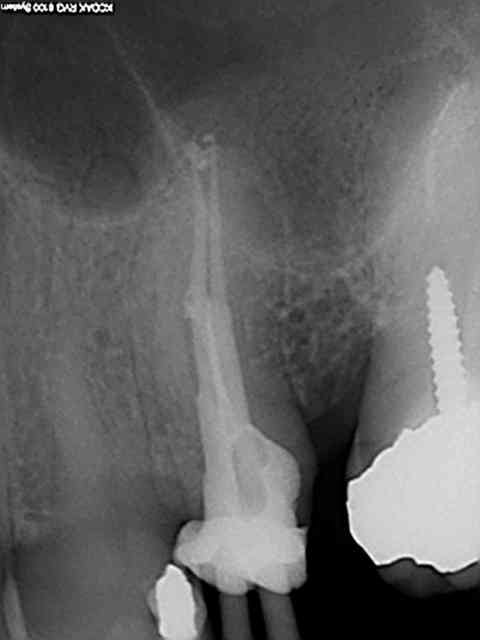

90 mn 2 molar endo + extrac 38. Un peu lent du à la difficulté à anesthésier (30 mn). les crochets apicaux traités comme si ils n'existaient pas avec le r25.

les 6 canaux avec le même r25. Attention toutefois je m'y suis repris à plusieurs reprises pour envoyer le s1 à l'apex (alternance r25 s1) et une bonne ouverture des entrées au largo ainsi qu'une très large cavité d'accès. Je n'ai à ce jour jamais cassé de r25, mais jamais essayé avec les plots en plastique .)

cela n'était pas des petites racines lt 24-25 mm. Big up à la digue qui m'a apporté un très gros confort de travail et m'a fait gagner du temps. Il n'y a que les imbéciles qui ne changent pas d'avis.

Maintenant pour peaufiner l'action du sx avant le passage du s1 un petit coup de r25 pour progresser d'avantage n'est pas interdit (pas de fausse route avec pour l'instant)c'est ce que j'ai fait sur ces 2 molaires ou la radio préop laissait présager un peu de sport. )))

connais pas. Mais une de plus 30 mn, résultat reproductible à un train de sénateur, po pom, po pom.) Radio cone en place facultative mais bon des fois je coupe le bout du cone..